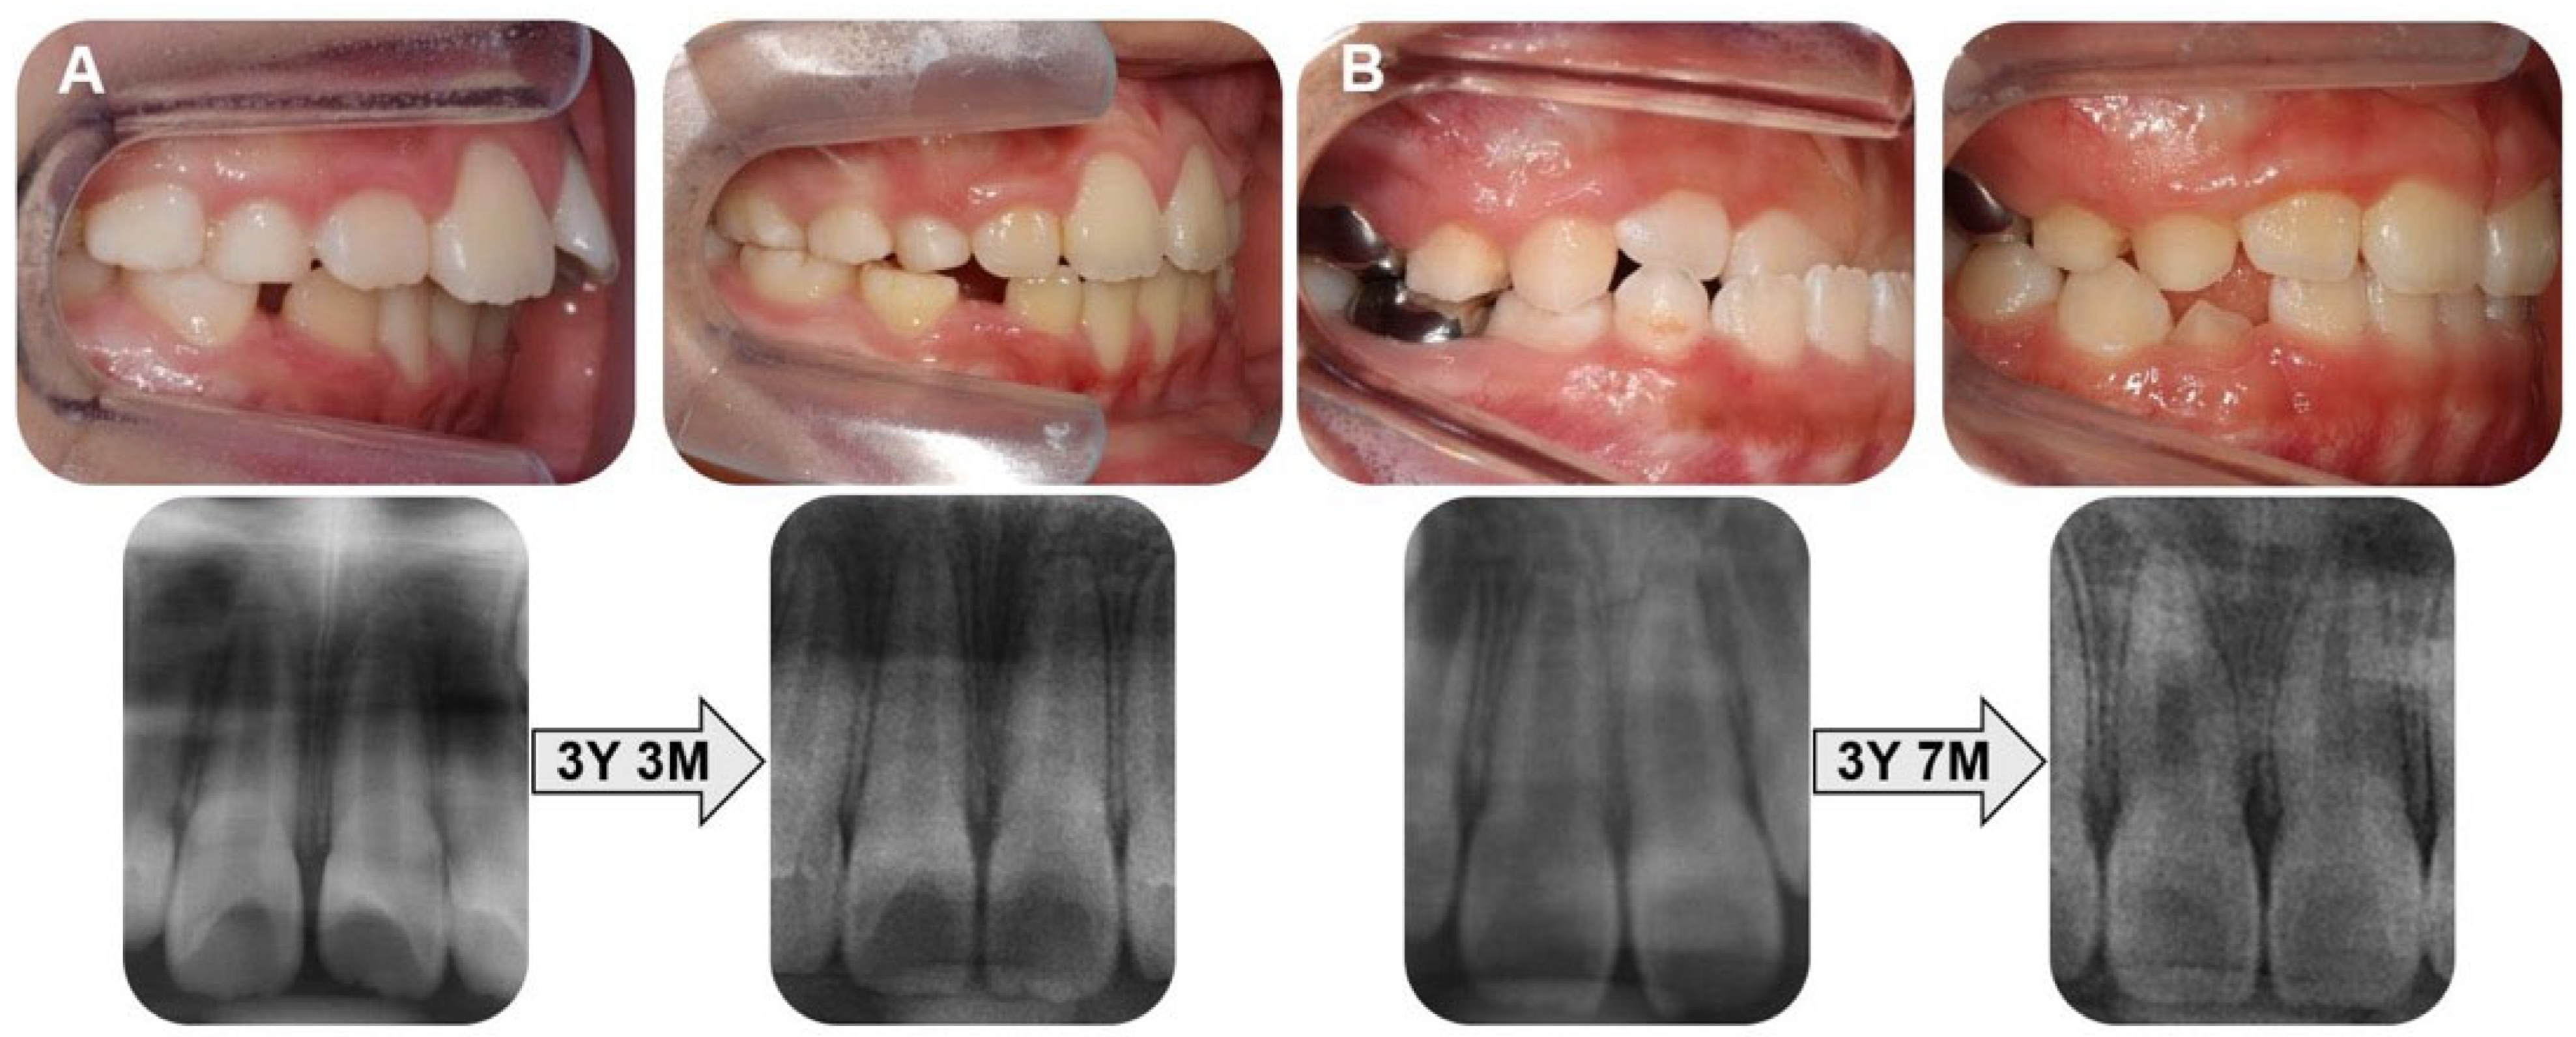

- Wan, J.; Zhou, S.; Wang, J.; Zhang, R. Three-dimensional analysis of root changes after orthodontic treatment for patients at different stages of root development. Am. J. Orthod. Dentofac. Orthop. 2023, 163, 60–67. [Google Scholar] [CrossRef]

- Li, X.; Xu, J.; Yin, Y.; Liu, T.; Chang, L.; Tang, Z.; Chen, S. Association between root resorption and tooth development: A quantitative clinical study. Am. J. Orthod. Dentofac. Orthop. 2020, 157, 602–610. [Google Scholar] [CrossRef]

- Şeker, E.D.; Yağci, A.; Kurt Demirsoy, K.; Yüzüak, E.N. A radiographic comparison of the root length and area after Class II treatment with two different functional appliances. Bezmialem Sci. 2020, 8, 321–329. [Google Scholar] [CrossRef]